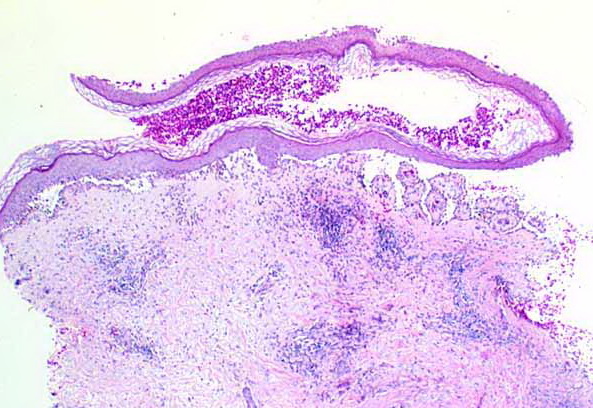

Pemphigus vulgaris develops primarily in older individuals, presenting with large and flaccid bullae. They break easily and leave denuded areas that tend to increase in size by progressive peripheral detachment of the epidermis, leading in some cases to widespread cutaneous involvement. The lesions characteristically involve the oral mucosa, scalp, midface, stemum, groin, and pressure points. Oral lesions  are almost invariably present and may be the first manifestation of the disease (10% of cases) . Before corticosteroids became available, the mortality of this disease was high because of fluid loss and superinfection.

The earliest recognized change may be either eosinophilic spongiosis rarely or, more commonly, “spongiosis” in the lower epidermis . This spongiosis may actually represent the earliest manifestation of acantholysis rather than true spongiosis as defined earlier. Acantholysis leads first to the formation of clefts and then to blisters in a predominantly suprabasallocation . The intraepithelial acantholysis may extend into adnexal structures or occasionally be higher in the stratum spinosum. The basal keratinocytes, although separated from one another through the loss of attachment, remain firmly attached to the dermis like a “row of tombstones.” Within the blister cavity, the acantholytic keratinocytes, singularly or in clusters, have rounded condensed cytoplasm about an enlarged nucleus with peripherally palisaded chromatin and enlarged nucleoli. In some patients, there are varying quantities of antidesmoglein 1 and antidesmoglein 3 antibodies, leading to variable planes of acantholysis. There is little inflammation in the early phase of blister formation. If present, it is usually a sparse, lymphocytic perivascular infiltrate accompanied by dermal edema. However, if eosinophilic spongiosis is apparent, numerous eosinophils may infiltrate the dermis. The phenomenon of eosinophilic spongiosis occurs occasionally in other blistering diseases, particularly in their early phases, including acute contact dermatitis, pemphigus foliaceus, bullous pemphigoid, herpes gestation is, drug eruptions, spongiotic arthropod bite reactions, and transient acantholytic dermatosis. Several important changes ensue as the lesions age. First, a mixed inflammatory cell reaction consisting of neutrophils, lymphocytes, macrophages, and eosinophils may develop. Because of the instability of the blister roof, erosion and ulceration may occur. Older blisters may also have several layers of keratinocytes at the blister base because of keratinocyte migration and proliferation. Last, there may be considerable downward growth of epidermal strands, giving rise to so-called villi (Fig. 9-9D). The evaluation of patients with only oral lesions is difficult, because intact blisters are rarely encountered due to the trauma of mastication, and biopsies may show only erosion and ulceration. Indeed, it is best to sample the edge of a denuded area with intact mucosa in an attempt to demonstrate the typical pathologic changes. Clinicians frequently cannot distinguish between an ulcer and the intact mucosa, as both are often white and shaggy. In patients with only oral lesions, biopsies of intact oral mucosa for DIF testing are more sensitive than biopsies of lesions for routine light microscopic evaluation. Therefore, biopsy from the normal maxillary and upper buccal mucosa is necessary when there is extensive ulceration. Cytologic examination using a Tzanck preparation is useful for the rapid demonstration of acantholytic epidermal keratinocytes in the blisters of pemphigus vulgaris. For this